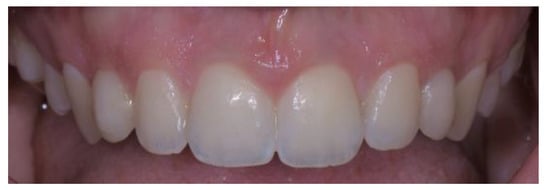

- Case 2:

- Case 3:

- Case 4: